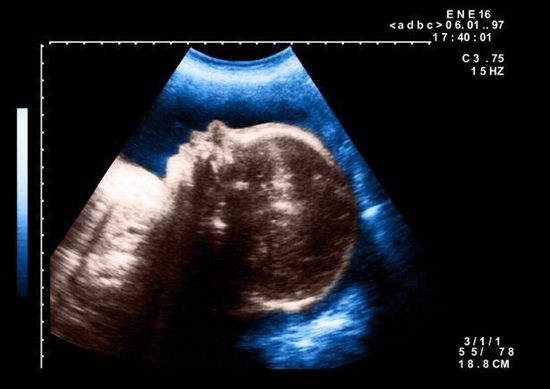

据英国《每日邮报》报道,当地时间10月6日,埃及的一家私人医院El Senbellawein接生一个罕见的缺陷婴儿,他只有一个眼睛,医生检查后预测,该婴儿活不过几天。这个畸形的婴儿让人想起希腊神话中只有一只眼睛的巨人。

据医生称,婴儿可能是在子宫里受到了放射物的影响。

这名畸形婴儿出生在埃及东北部小镇的一家私人医院。图为该医院示意图。